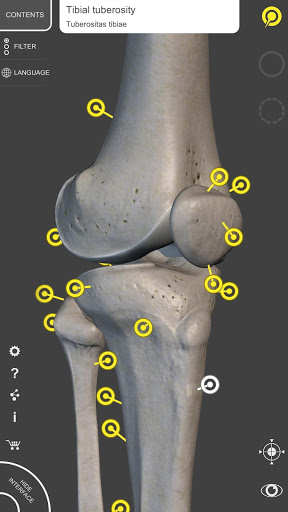

Mỗi xương của bộ xương người đã được tái tạo ở dạng 3D, bạn có thể xoay và phóng to từng mô hình và quan sát chi tiết từ mọi góc độ.

Bằng cách chọn mô hình hoặc ghim, bạn sẽ được hiển thị các thuật ngữ liên quan đến bất kỳ bộ phận giải phẫu cụ thể nào, bạn có thể chọn từ 12 ngôn ngữ và hiển thị các thuật ngữ bằng hai ngôn ngữ cùng lúc.

HÌNH GIẢI PHẪU 3D CÓ ĐỘ CHI TIẾT CAO

• Hệ thống xương

• Mô hình 3D chính xác

• Bề mặt của bộ xương có kết cấu độ phân giải cao lên đến 4K

• Xoay và Phóng to mọi mô hình trong không gian 3D

• Ghim tương tác cho phép trực quan hóa thuật ngữ liên quan đến mọi chi tiết giải phẫu